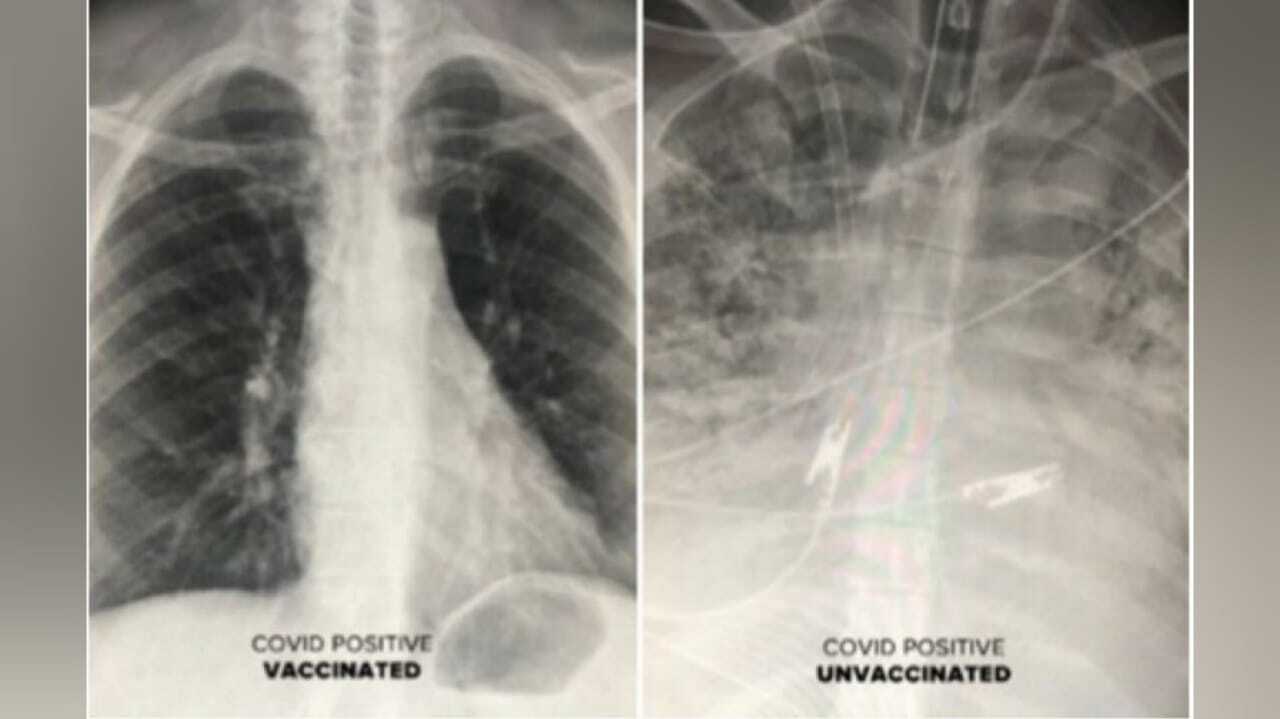

Hasil rontgen paru-paru pasien Covid-19 yang sudah divaksin (kiri) vs belum divaksin (kanan). Foto: Dok Dr. Sam Durani/ Republika

Ia membagikan perbandingan rontgen kondisi paru-paru pasien positif Covid-19 yang sudah divaksinasi dengan yang belum divaksinasi. Setelah diamati, keduanya mempunyai perbedaan yang mencolok.

Hasil rontgen pasien yang telah divaksinasi menunjukkan udara lebih banyak mengalir, dengan sebagian besar paru-paru berwarna hitam. Hal ini menunjukkan tidak ada kerusakan. Sebaliknya, hasil rontgen dari pasien yang tidak divaksinasi menggambarkan paru-parunya tersumbat, kemudian membatasi aliran oksigen ke seluruh tubuh.

“Satu-satunya orang yang benar-benar sakit adalah orang yang tidak divaksinasi. Mereka sering kali membutuhkan ventilasi dan oksigen,” ujar dr. Durrani seperti dilansir Republika dari situs The Sun, Senin (25/10/2021).

“Pasien yang sudah divaksin dan terkena breakthrough infection (infeksi terobosan) dengan gejala sesak napas, kondisi mereka tidak seburuk pasien yang tidak divaksinasi. Bahkan breakthrough infection yang berakhir dengan pneumonia, CT scan mereka masih tidak seburuk pasien yang tidak divaksinasi,” sambungnya menjelaskan.